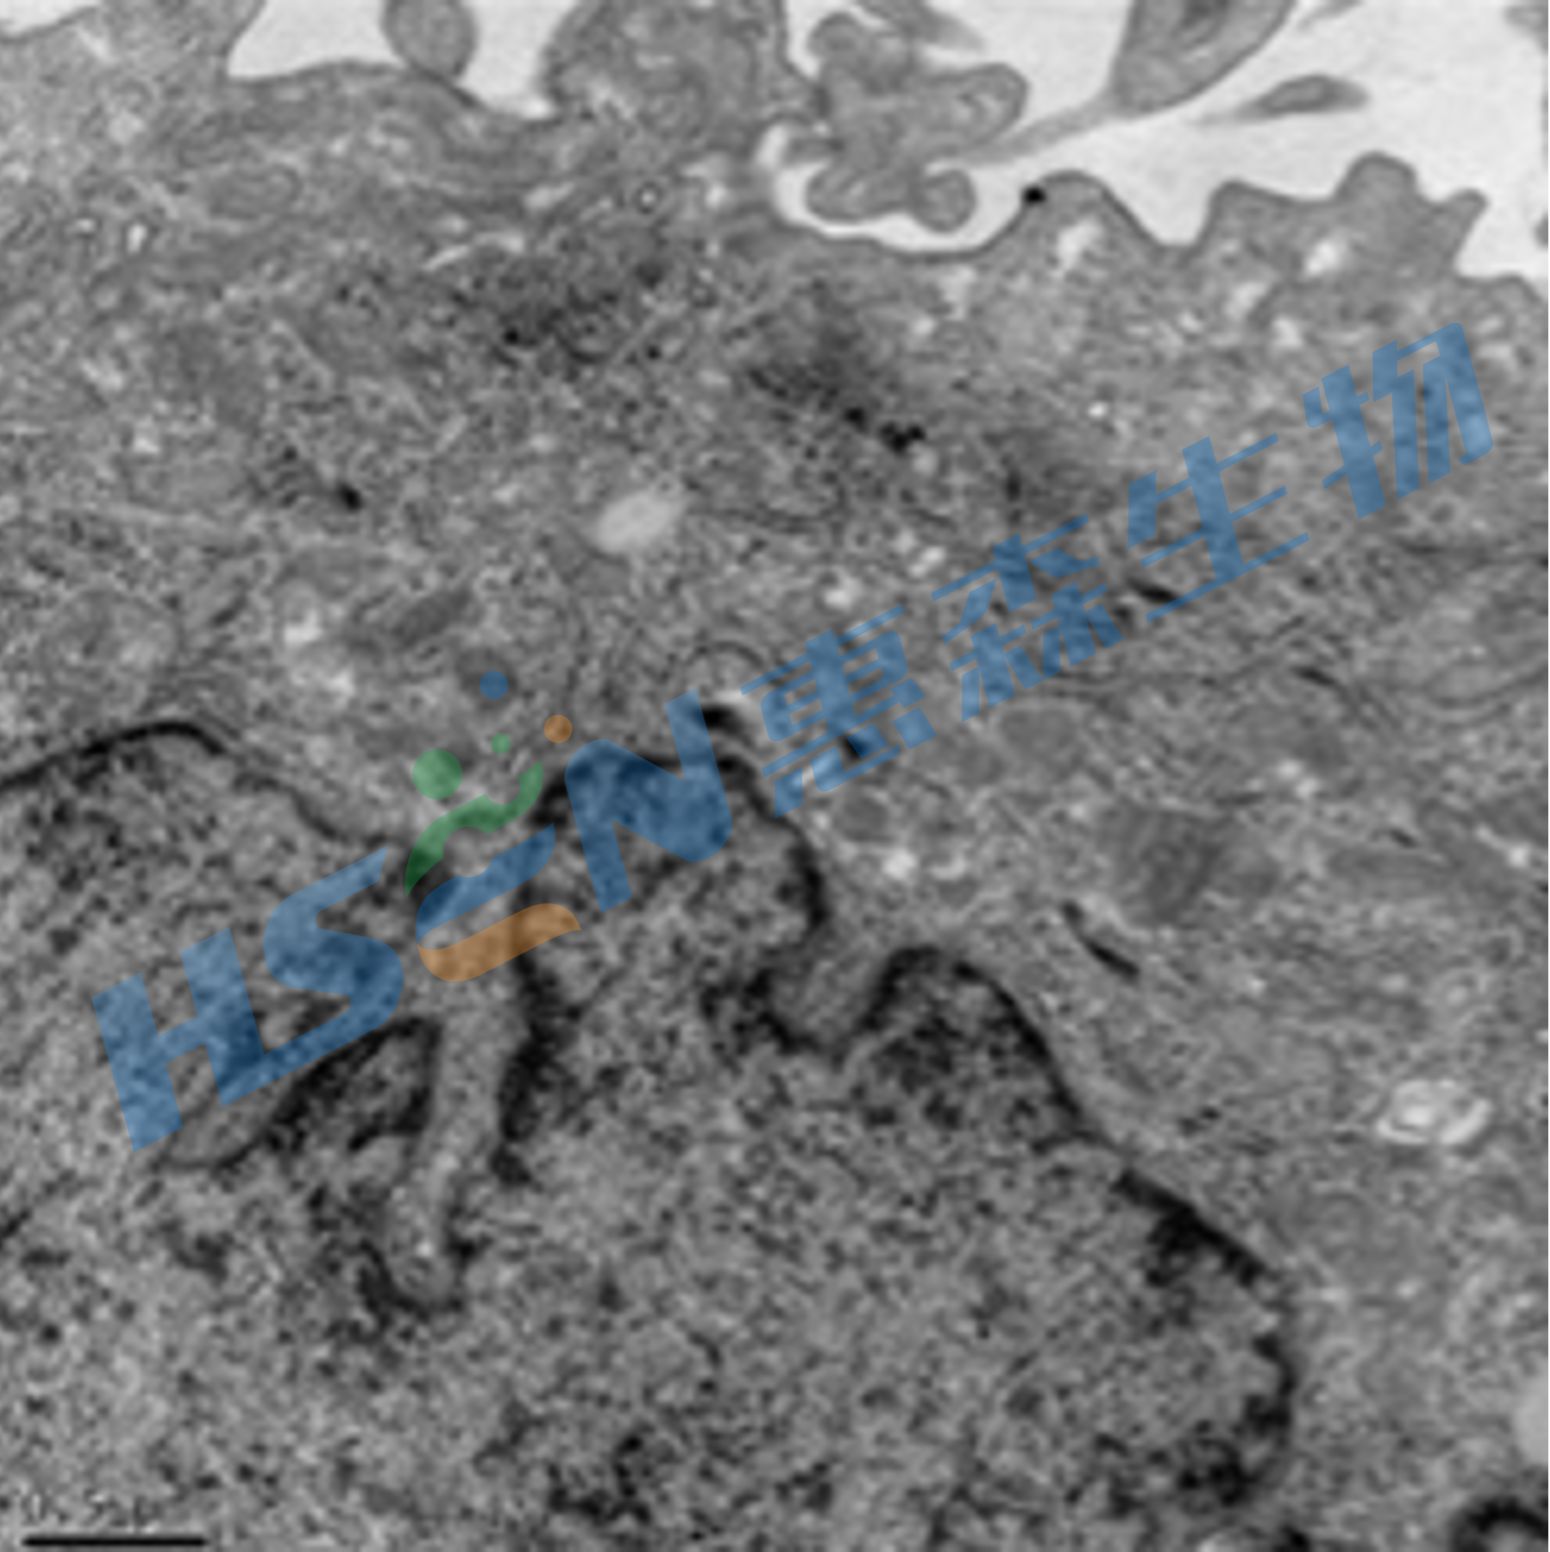

利用电子射线(或称电子束)穿透样品,而后经多级电子放大后成像于荧光屏。透射率高,可以用来观察组织和细胞 内部的超微结构以及微生物和生物大分子的全貌。能分辨0.1纳米以下的微细物质结构,放大倍数可达100万余倍。

结果示意图: